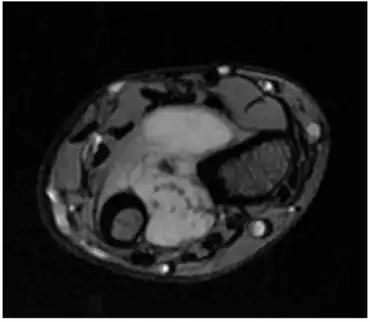

| Distal radioulnar joint shows calcified nodules consistent with synovial osteochondromatosis. | |